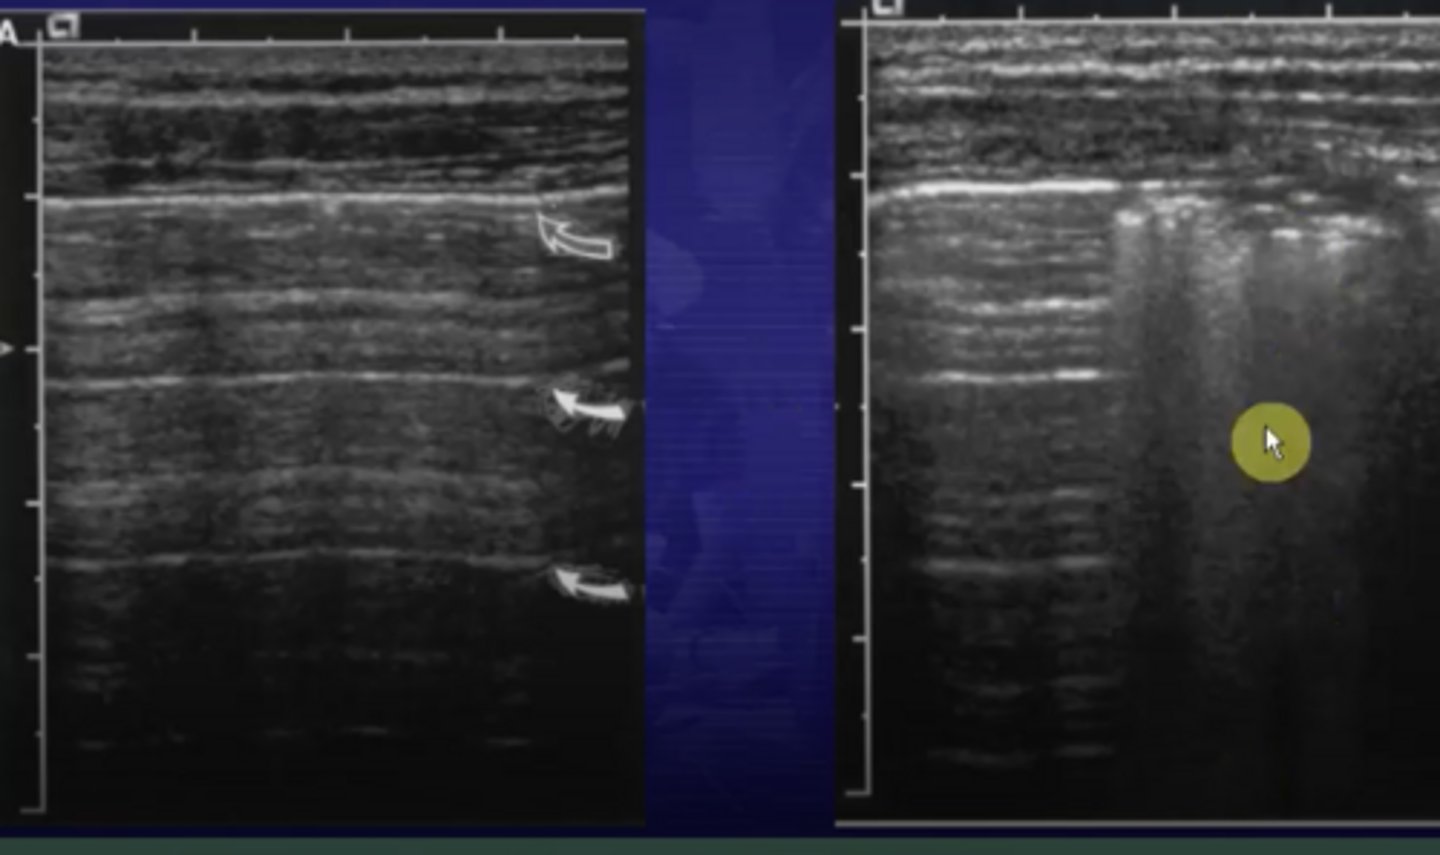

What is the sliding lung sign? Explain the normal and abnormal findings.

• If pleura is normal, will see visceral pleura (covering the lungs) slide across parietal pleura (covering the chest wall) when patient breathes

• If pneumothorax is present, sliding lung sign will be absent in area of pneumothorax

If a pneumothorax is present you will not see _________ you will see _______.

reverberation ; shadowing